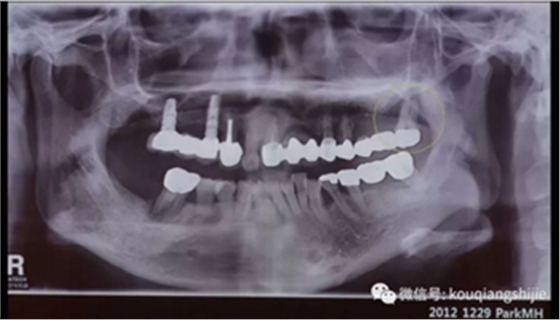

这个患者在2012年的时候#17已经是需要拔除的情况,但是因为患者要求保留,所以我们进行保守治疗

4年后患者再次就诊,要求拔出

这时候我们可以看到患牙周围已经没有任何骨壁。

我们看一下#27部位的拔牙创

你会觉得覆盖在拔牙创上部分的是肉芽组织吗?

我个人觉得不是,我觉得他就是上面我们定义的拔牙窝线性黏膜组织